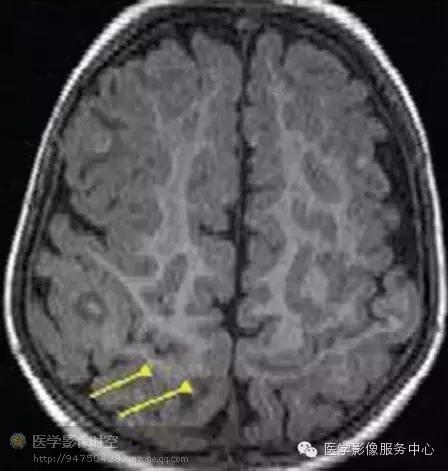

结节硬化是常染色体显性遗传病,具有多器官错构瘤。发生率为1/6000-12000。临床检查中,结节硬化的特征是面部血管瘤,智力低下,癫痫三联症。90%的结节硬化病人具有癫痫。相对部分病人具有抗药性。结节硬化累及中枢神经系统的典型表现是皮层结节,室管膜下结节和室管膜下巨细胞性星形细胞瘤。一般癫痫灶与结节和结节邻近的脑皮层有关。磁共振成像上容易识别皮层结节,根据髓鞘化程度显示为不同程度的的T1WI和T2WI信号异常。在新生儿,结节显示为皮层下T1WI高信号和T2WI低信号,6月龄以后,表现则正好反过来。

结节硬化病人伴发难治性癫痫的病人常常具有多发结节。因此准确识别引起癫痫活动的结节非常重要。单靠磁共振成像成像难以完成该工作。联合应用磁共振成像和脑电图数据,进行相关分析,有时候可以找到病变位置。最近,MR-PET融合图像和磁源成像能够提供结节硬化相关性癫痫灶的定位。发作间期MR-PET融合图像上具有癫痫活动的结节硬化病变显示为低代谢区,范围大于相关的磁共振成像信号异常区(例如年龄大于6月儿童的T2WI高信号区)(图7)

图7 继发于左侧颞叶前极的结节硬化结节的难治性癫痫

图7a横断FLAIR图像图像显示多发的皮层和皮层下结节(箭头)

图7b横断发作间期MR-PET融合图像显示左侧颞极大的低代谢区(箭)。术中脑皮层电图显示弥漫性代谢减低区,提示癫痫灶。 发作间期磁源成像可以通过配准癫痫样放电与磁共振成像解剖图像方法显示癫痫性结节。

图8 继发于右顶叶后内面的结节硬化结节的难治性癫痫。

图8a横断FLAIR图像图像显示多发的皮层和皮层下结节(箭)

图8b横断发作间期MR-PET图像显示多发的低代谢区,与结节硬化结节吻合。没有发现与FLAIR图像上局部结节不成比例的低代谢区。

图8c横断发作间期磁源成像显示继发于右后顶叶结节的癫痫样活动。